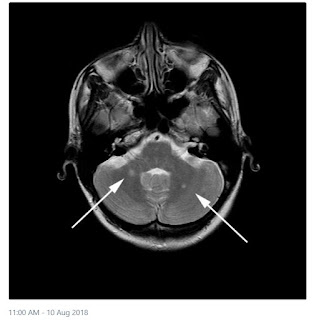

Magnetic resonance imaging (MRI) is the key prognostic tool in people with a clinically isolated syndrome (CIS). There is increasing interest in treating people following a CIS in the hope that conversion to multiple sclerosis (MS) will be prevented and future disability reduced. So far, the prognostic value of MRI for disability following a CIS has not been evaluated systematically. We systematically searched MEDLINE and EMBASE. Cohort studies were selected if they reported associations of MRI and disability following a CIS, included at least 50 people with a CIS at baseline, had at least 5 years of follow-up and obtained at least one structural MRI measurement (T1 lesions, T2 lesions, T1 contrast enhancing lesions or brain atrophy). We assessed the studies for quality and rated the completeness of MRI reporting. In total, 13 studies were identified reporting on the following: T2 lesion number and volume, T2 infratentorial lesion number and volume, T1 contrast enhancing lesions and grey matter fraction. T2 brain lesion number determined soon after the occurrence of a CIS was associated with disability progression after 5 – 7 years, with an increased risk when 10 or more lesions were present. Infratentorial lesions were also associated with a higher risk of subsequent disability. The number and distribution of MRI-visible lesions soon after a CIS is associated with disability later on, and may offer additional useful information when making treatment decisions in people with early MS. Further work is required to determine if other measures have a higher predictive potential. This article is protected by copyright. All rights reserved.